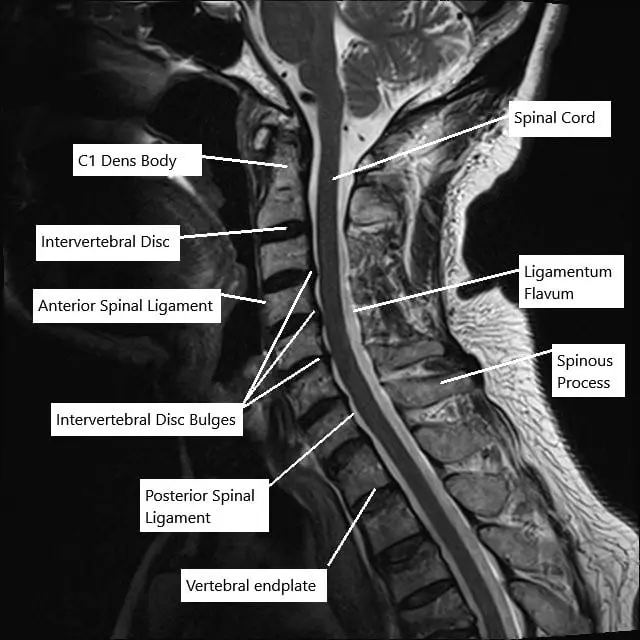

MRI of the cervical spine in sagittal section showing disc herniations.

The cervical spine consists of seven vertebrae that protect the spinal cord and allow head and neck motion. Between the vertebrae are discs that absorb shock and provide flexibility. Small openings between bones (foramina) let nerves branch from the spinal cord to the shoulders, arms, and hands.

When the canal or foramina become smaller, the spinal cord or nerves can be squeezed, leading to pain and neurological symptoms.

Imaging studies may include:

- X-rays: Show bone alignment and narrowing between vertebrae.

- CT scans: Provide detailed views of bone spurs and ligament thickening.

- MRI scans: Offer the best look at soft tissues, discs, and the spinal cord itself.

MRI findings help determine whether symptoms come from nerve or spinal cord compression and guide treatment decisions.